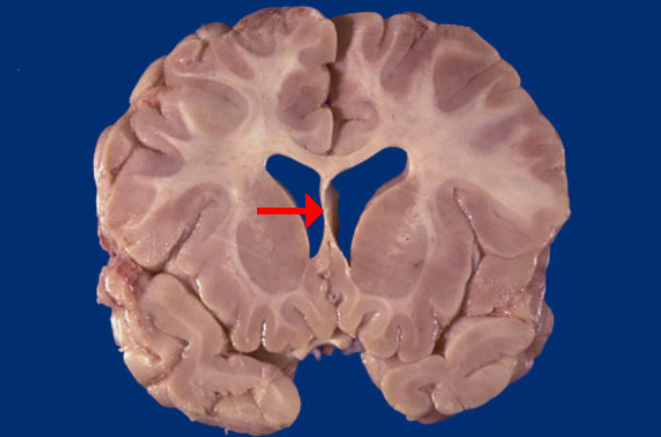

Label this brain structure

Caudate nucleus

Label this brain structure

Putamen

Label this brain structure

Globus pallidus

Label this brain structure

Amygdala

Label this brain structure

Septum pellucidum